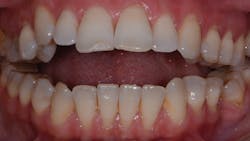

The following clinical case study will demonstrate both of these important principles. A 42-year-old female presents for evaluation of progressive facial and dental occlusion changes (figure 1).

TMD/occlusion disorders:Positive for severe degenerative joint disease (DJD); severe anterior open-bite malocclusion